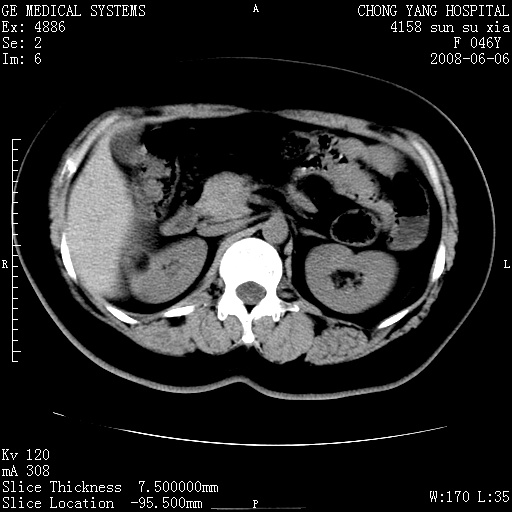

标题: CT13886:F 40Y, 外侧的CT值-60 内侧的25HU. 未作增强 [打印本页]

标题: CT13886:F 40Y, 外侧的CT值-60 内侧的25HU. 未作增强

考虑:右肾错构瘤。

右肾平滑肌脂肪瘤并肾囊肿

右肾血管平滑肌脂肪瘤并肾囊肿(后者请排除容积效应,可结合超声)

右肾血管平滑肌脂肪瘤并肾囊肿(后者请排除容积效应,可薄层扫描或结合超声)

根据影像表现,基本可确诊!